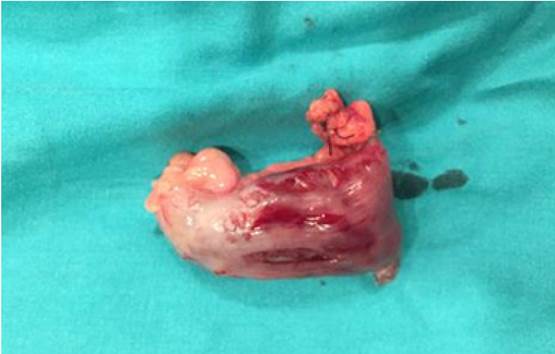

El paciente, ante un cuadro de invaginación intestinal, fue intervenido mediante laparotomía exploradora, comprobándose la presencia de un divertículo de Meckel. A continuación se procedió a la resección del mismo (Figuras 1 y 2) y se realizó una apendicectomía profiláctica. La evolución postoperatoria fue favorable y el paciente fue dado de alta en unos días, permaneciendo asintomático en la actualidad. El informe anatomopatológico confirmó la existencia del divertículo de Meckel en un segmento de intestino delgado.